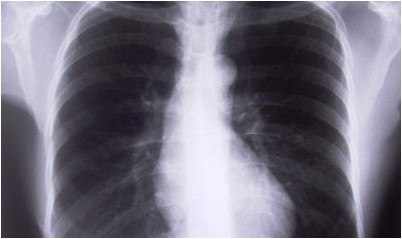

Доктор, с подозрением относящийся к стенокардии, закажет один либо больше следующих анализов:Электрокардиограмма (EKG) – делает запись электрической активности сердца и может найти, в то время, когда сердце оголодало для кислородаАнализ стресса – показания кровяного давления и EKG, тогда как больной увеличивает физическую активностьРентген грудной клетки – дабы видеть структуры в груди